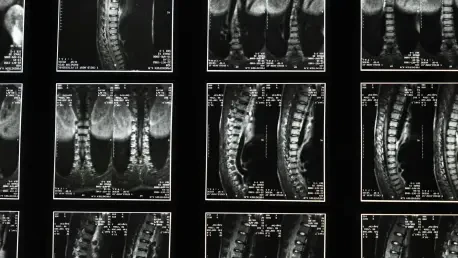

Imagine a world where spinal injuries, often synonymous with long recovery times and persistent pain, could heal faster and more effectively through the body’s own natural processes, enhanced by cutting-edge technology. Spinal and orthopedic trauma affects millions globally, with traditional treatments relying heavily on invasive surgeries and prolonged rehabilitation. However, a groundbreaking innovation in medical devices is emerging as a potential game-changer. A recent partnership between a Boston-based venture capital firm and a pioneering startup has brought attention to piezoelectric implants—devices that harness mechanical stress to generate bioelectrical signals, stimulating tissue regeneration. This technology promises to transform the landscape of spinal recovery by accelerating healing and improving patient outcomes. As the healthcare industry increasingly turns to regenerative solutions, the spotlight on such advancements raises critical questions about their feasibility, impact, and timeline for widespread adoption.

At the heart of this innovation lies a novel approach that blends biology with biomechanics, offering a fresh perspective on treating spinal injuries. Piezoelectric implants, developed by a forward-thinking medical device startup, convert mechanical stress from everyday movements into electrical signals that stimulate the body’s natural repair mechanisms. Unlike traditional implants that merely provide structural support, these devices actively promote tissue regeneration, potentially reducing recovery times for patients with complex spinal or musculoskeletal conditions. The startup behind this technology has secured significant funding from a healthtech-focused venture capital firm, enabling crucial steps like product refinement and regulatory approval processes. This financial backing underscores a growing confidence in the potential of regenerative therapies to address unmet needs in orthopedic care, where current solutions often fall short in restoring full functionality. As research progresses, the medical community watches closely to see if this approach can deliver on its promise of faster, more effective healing.